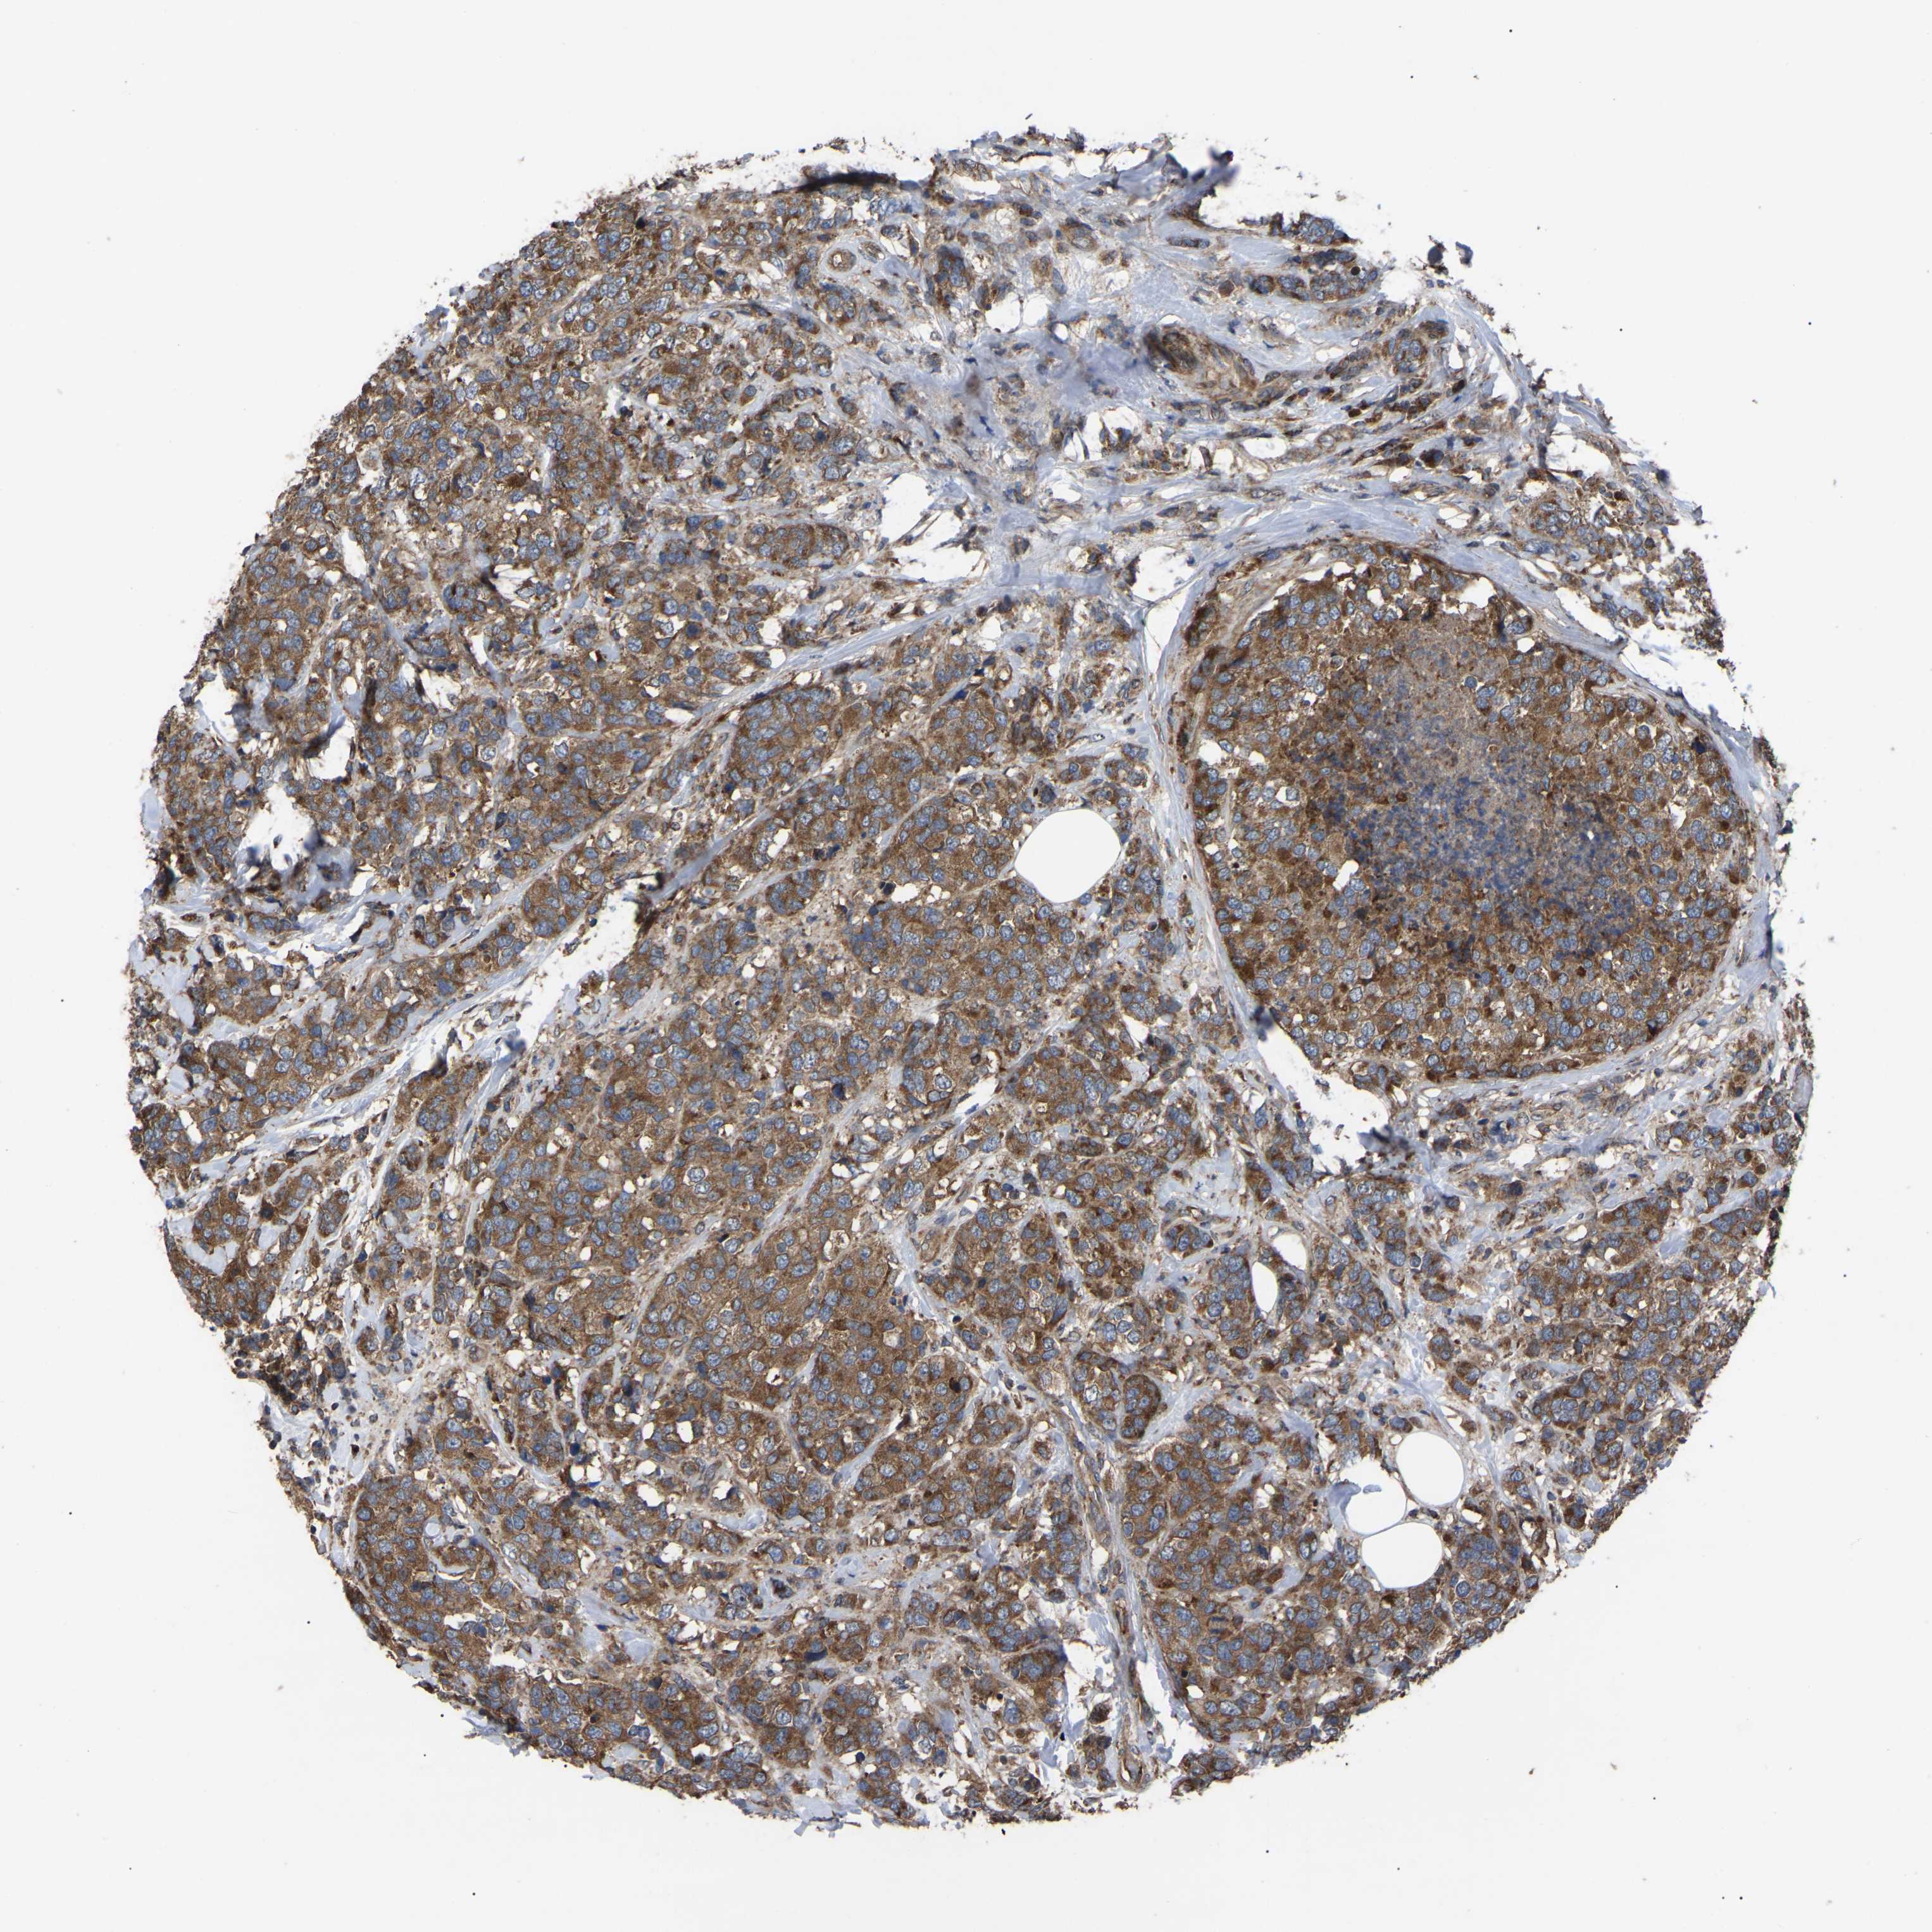

CANCER BREAST CANCER Show tissue menu

BRCA TCGA BRCA VALIDATION PROTEIN EXPRESSION